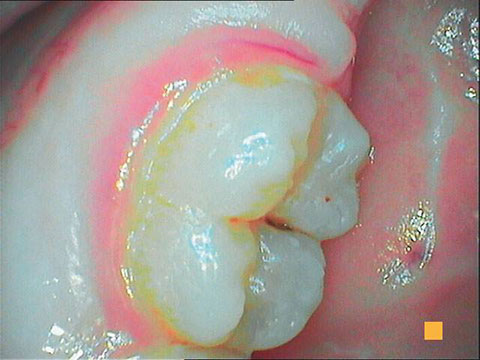

SoproCARE was developed to answer the needs of the dental professional during caries detection, prophylaxis and periodontal treatment in the clinical environment. Utilizing patented fluorescence technology, SoproCARE illuminates dental tissue to reveal occlusal caries, plaque, tartar and gingival inflammation. In addition, SoproCARE can be used as an intraoral camera, providing the dental professional with all of the necessary tools to perform a complete and time-efficient oral examination.